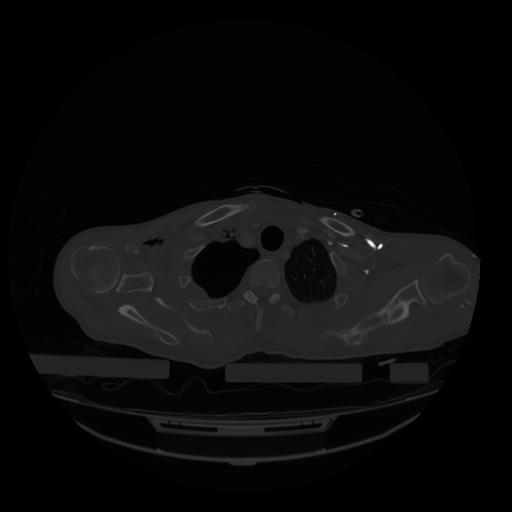

28 CUERPO,CE,Vol,2.0,CUERPO,,